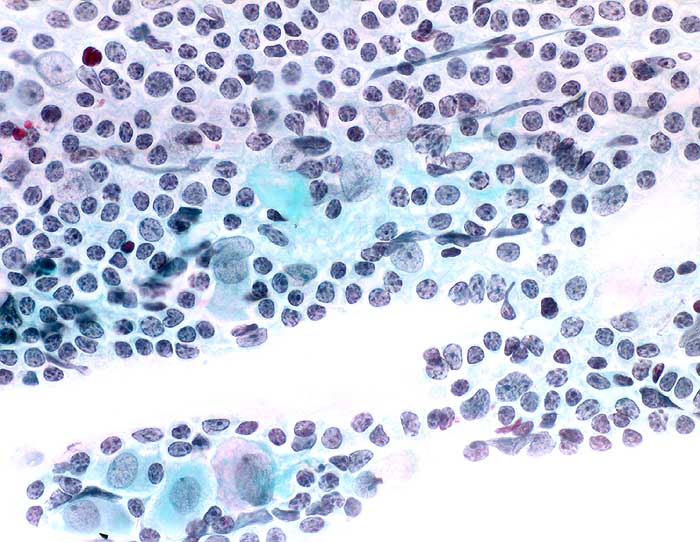

g/ Follikuläre Zervizitis

Follikuläre Zervizitis

Möglicherweise besteht bei dieser speziellen Form der Zervizitis eine Assoziation mit Chlamydieninfektionen. Die Entzündung ist durch ein dichtes lymphozytäres Infiltrat mit grossen Follikeln und hyperplastischen Keimzentren charakterisiert. Die Ausstriche enthalten entsprechend zahlreiche einzeln liegende kleine und grosse Lymphozyten, Keimzentrumszellen und Kerntrümmermakrophagen. Die Entzündungszellen kommen bevorzugt im endozervikalen Abstrich vor, wo sie im Zervixschleim typische Zellstrassen bilden.